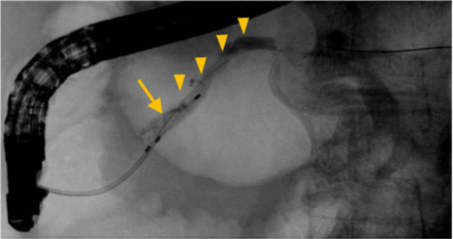

【内視鏡による膵石の除去】

内視鏡を使って膵管(矢頭)の中に造影剤を注入し、膵石の位置を確認する。膵石はバスケット(矢印)という道具を使って、腸の中につかみだす。